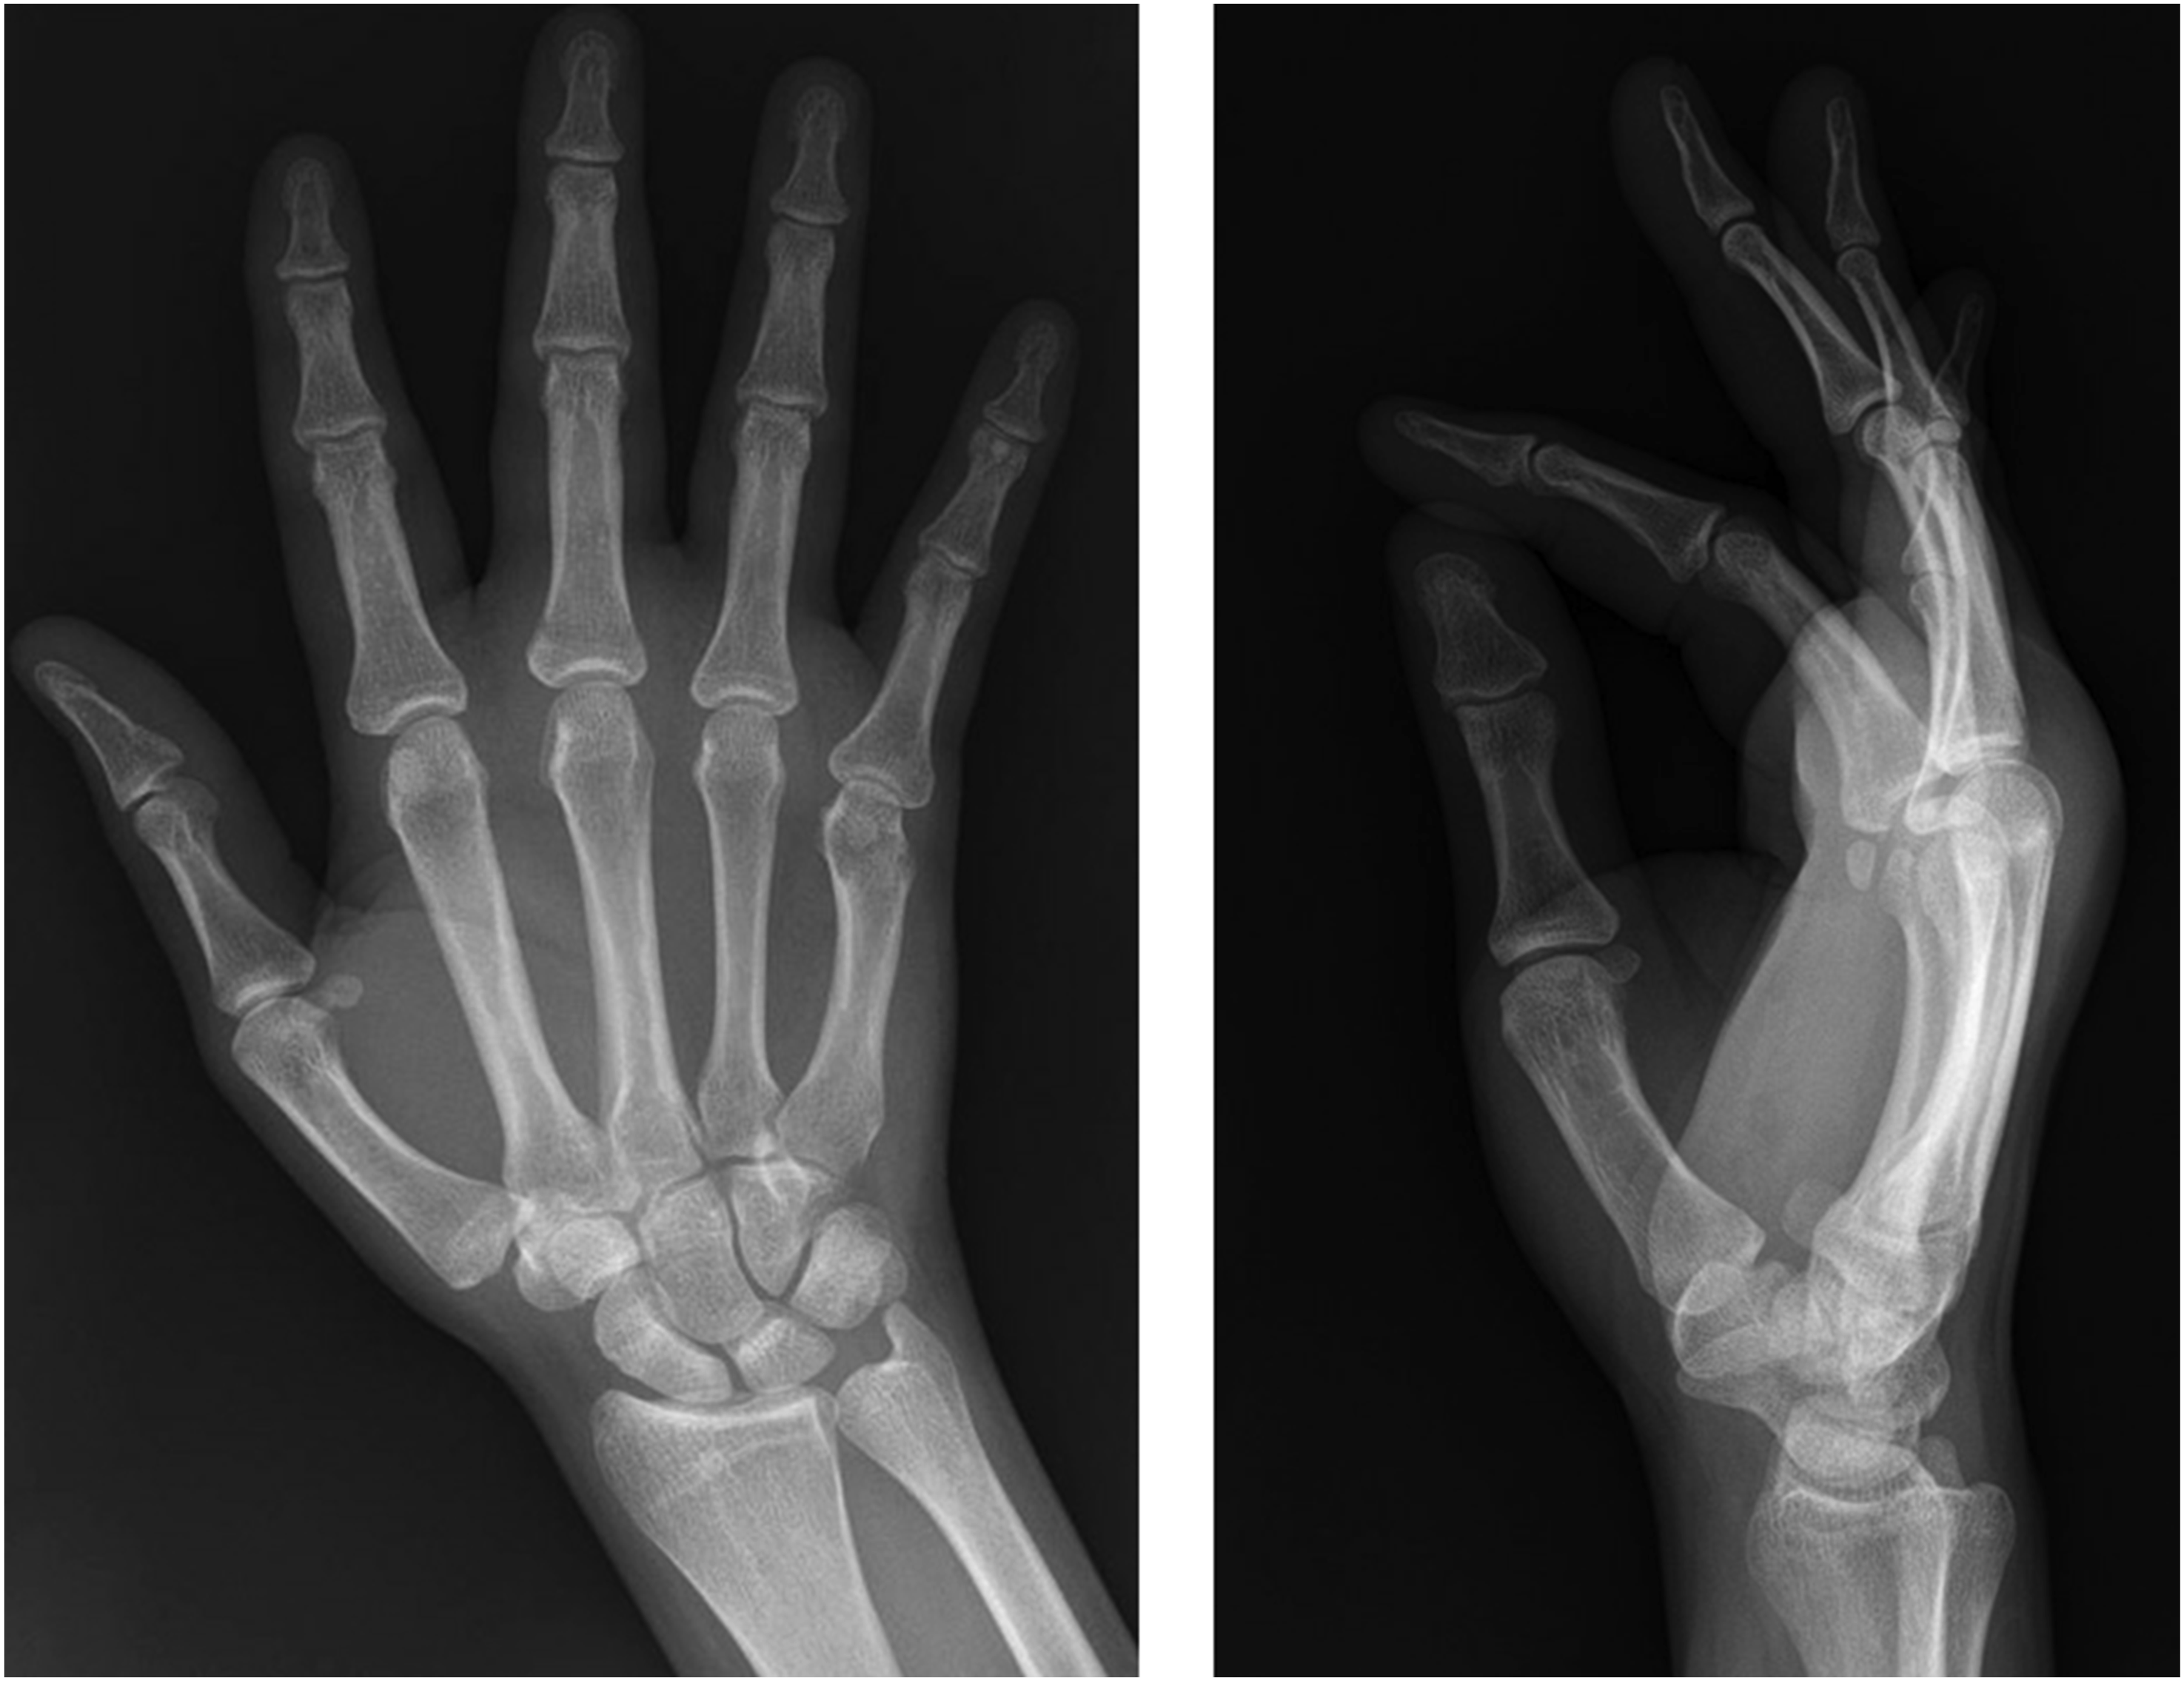

Two months later, he developed new-onset migratory polyarthritis involving the left elbow, bilateral ankles, knees, and small joints of both hands. At this time, the patient did not have any abdominal symptoms. Physical examination revealed joint swelling and tenderness. Radiographs of the right hand (Figure 1) and left elbow (Figure 2) obtained at this time demonstrated only soft tissue swelling, with no radiographic evidence of erosive or inflammatory arthritis, focal bone lesions, or bone infarction. MRI of the left elbow showed posterior subcutaneous and soft tissue edema with associated triceps muscle edema, a small joint effusion and mild bone marrow edema at the olecranon process (Figure 3). Synovial fluid aspirated from the left elbow showed mildly elevated white blood cell count (3000 cells/mm3), but Gram stain, culture, and crystal analysis were negative. Laboratory tests showed elevated ESR and CRP, normal serum uric acid, creatine kinase, and complement (C3 and C4) levels. Antinuclear antibody and rheumatoid factor were negative. Urine tests for Radiographs of the right hand demonstrating soft tissue swelling predominantly about the metacarpophalangeal joints. No osseous erosions, no focal lytic or sclerotic bone lesion. Radiographs of the left elbow demonstrating mild soft tissue swelling at the posterior elbow. No osseous abnormalities. Axial STIR MR images of the left elbow demonstrate subcutaneous edema, triceps muscle edema, small joint effusion and mild bone marrow edema at the olecranon process.